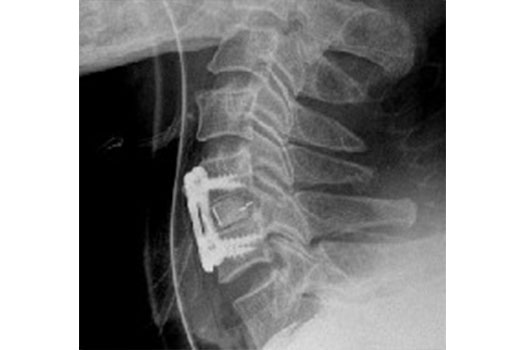

La chirurgie de la hernie discale cervicale se réalise par une voie d'abord antérieure, et consiste en une résection de la hernie, associée à une arthrodèse.

Corporectomie cervicale